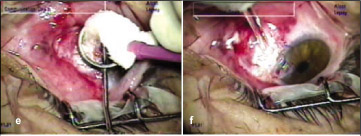

6. Após 40 segundos absorve-se o álcool com uma esponja seca de celulose (Figura 2e);

7. Irrigação copiosa da área com solução salina balanceada (Figura 2f);